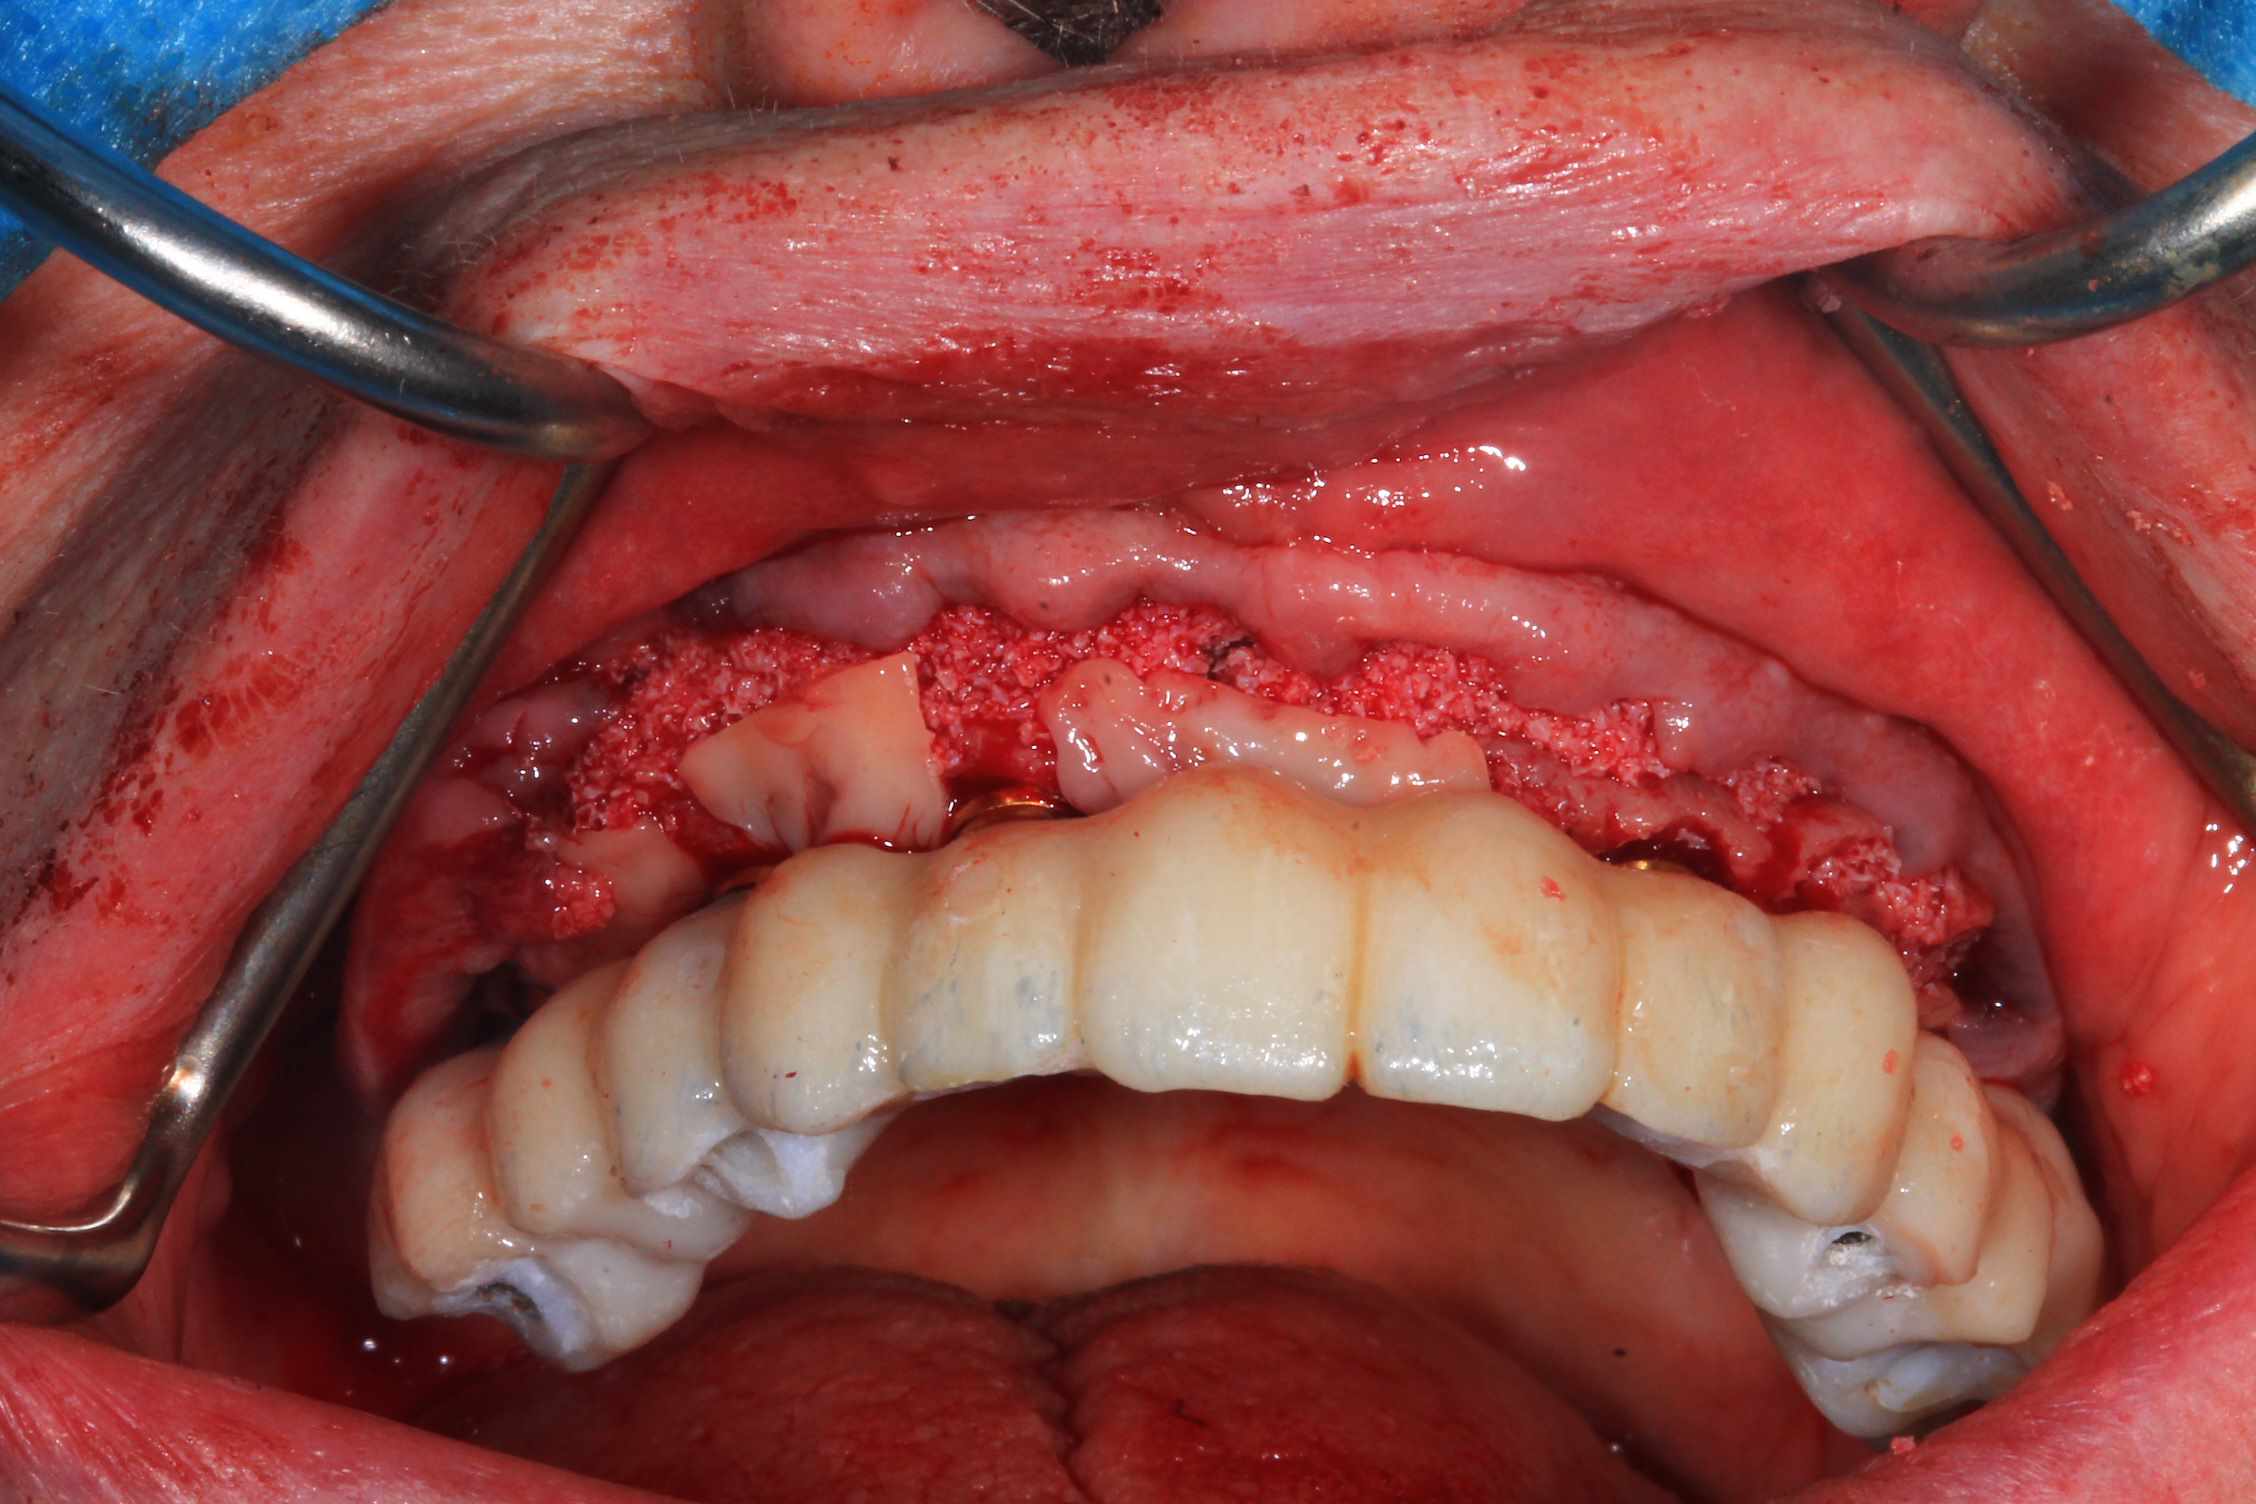

Mais celui la est tout chaud ( de vendredi dernier ) et j'ai regarder le temps que j'ai mis ( beaucoup plus complexe, donc plus long ). on va l'appeller Cas 2.

3 h de planif, modélisation du guide, puis 2 h environ pour la simulation de la chir , le modelisation et l'impression du bridge, qui tombe pile, zero retouche occlusale.

Avec un plan de traitement qui est suceptible de débat :)

Cas 2 , suite : avec une saussage au passage..

le patient arrive a 9 h, Prise de sang, PRF, injection de corticoïde, anesthésie et installation au bloc. Premier coup de bistouri a 9h30. Dernière suture a 11h30.

Chir le vendredi matin. au vu de la possibilité de reculer pas mal les implants postérieurs, je trouvais qu'il y avait trop de porté entre les implants : je pars donc sur 6 implants.

Mais malgré les gros renforts, le guide résine n'est pas assez rigide : impossible de poser le bridge en immédiat. obligé de fraiser le bridge ( j'aurais du en prévoir un autre évidé, ce que je prévois pour lundi prochain ) et de mettre des piliers provisoires : 40 m de travail de labo en plus..